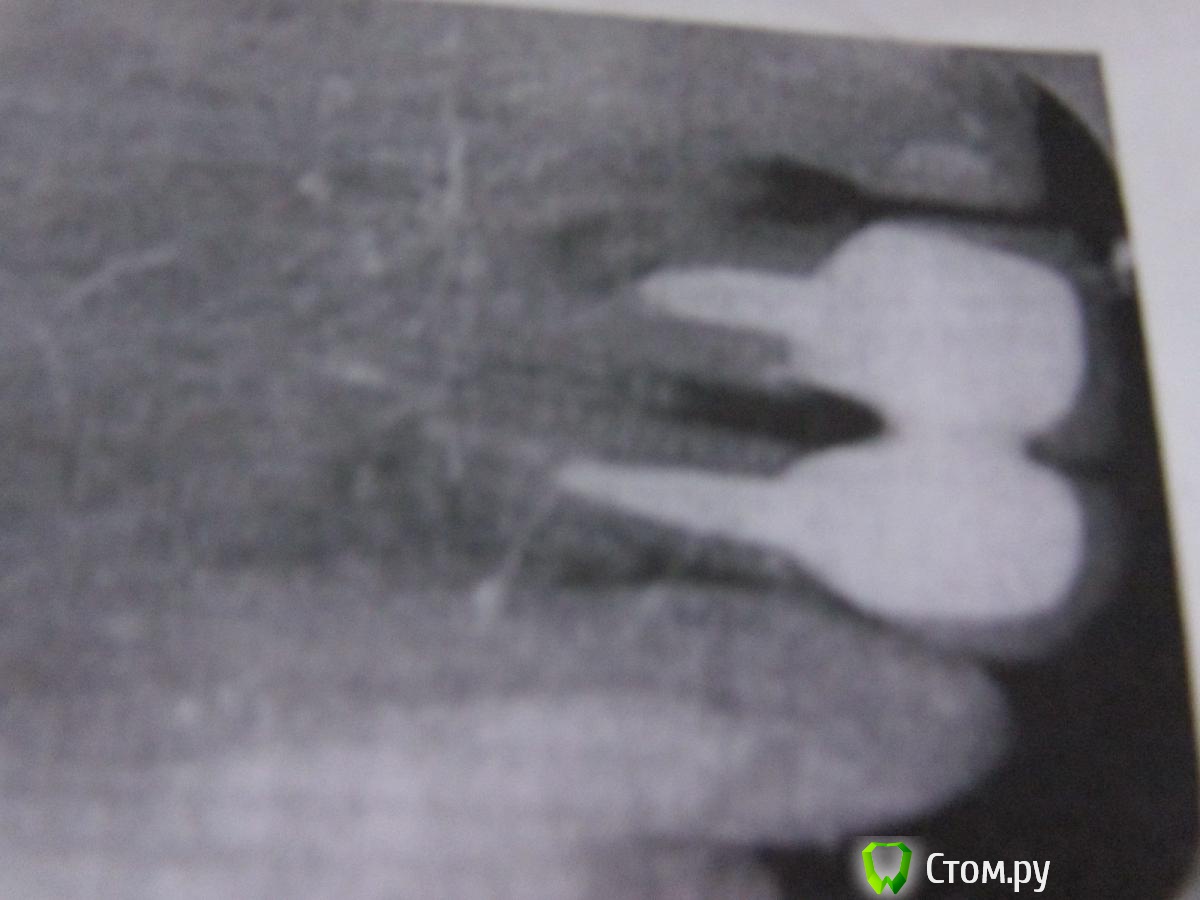

Татьяна87 Опубликовано 5 мая, 2014 Поделиться Опубликовано 5 мая, 2014 Добрый день! Прошу совета, что лучше сделать в моей ситуации.У меня стоит вопрос протезирования 4 передних верхних зубов. На 1 и 2 уже стоят коронки МК+металлические вкладки. Коронки довольно быстро (года через 2) отошли и появилась щель между единицами. Врач говорит, что вопрос в корнях (много лет назад была резекция кисты на корнях). Кроме того, десна под коронками потемнели.После консультации у трех специалистов принято решение делать четыре передних зуба (двойка депульпирована, единица с большими пломбами), также оба зуба под вкладки.Двое врачей рекомендовали сделать БМК, т.к. десна у меня потемнели от металлокерамики. Третий врач сказала, что БМК нельзя делать на металлические вкладки, т.к. они будут просвечивать, а удалить их можно только вместе с зубами. Потемнение десен она объясняет не материалом, а старым методом лечения зуба, после чего темнеют ткани.Кроме того, все рекомендуют делать слитную конструкцию, чтобы зубы не разъезжались.Конечно, мне бы хотелось БМК, т.к это выглядит более естественно, да и за раздельными коронками легче ухаживать с гигиенической точки зрения. Прошу дать совет Ссылка на комментарий

Korel Опубликовано 5 мая, 2014 Поделиться Опубликовано 5 мая, 2014 Здравствуйте. Для начала сделайте Кт (комп. томогр.)Ваши R - cнимки не оч. хорош. качества.Далее: нужна совместная консультация ортодонта+ортопеда+хирурга+пародонтолога . Если найдёте Дока в одном флаконе это бы лоб идеально.И конечно очный осмотр.Лично мне ,по представл. данным очень трудно что- то ответить конкретно, а гадать не хочется. Ссылка на комментарий